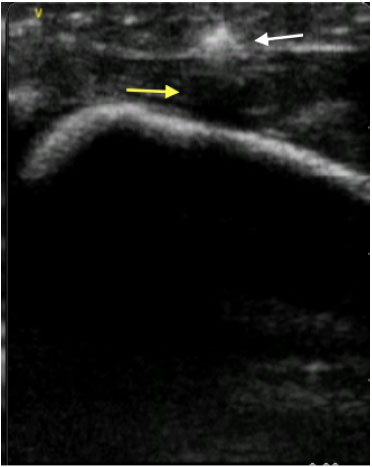

A maioria dos CE como a madeira, o plástico, o vidro e o metal são hiperecoicos quando vistos no ultrassom. 2 Tanto a madeira quanto o plástico são objetos com melhor visualização por ultrassom do que por radiografia simples. 18 Um estudo mostrou que o ultrassom foi capaz de detectar fragmentos de madeira de até 2,5mm com 87% de sensibilidade e 90% de especificidade. (Figura 1)19 Dependendo do tamanho e da densidade, eles podem gerar uma sombra acústica posterior que auxilia em sua localização. Os vidros e os metais geralmente possuem artefatos de reverberação, e aparecem como linhas hiperecoicas repetitivas profundamente ao objeto (Figura 2). Itens metálicos arredondados ou pequenos tipicamente geram a “cauda de cometa”, um tipo específico de artefato de reverberação. 2 Pode haver líquido inflamatório hipoecoico com coleção de fluido ao redor do CE, o que é chamado de sinal do halo. Ainda, isto pode representar edema, abcesso ou tecido de granulação. 16 Geralmente, o halo se desenvolve após 24h como resultado de resposta inflamatória local, e auxilia na visualização do CE. 3